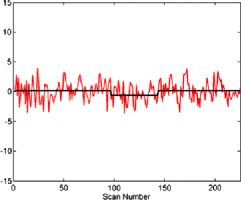

The subject in Figure 3 seems to exhibit strong deviations from stationarity—in fact, the -value associated with this subject is below based on the bootstrap test given in Section 7. It should be stressed that the change detection is a global hypothesis test combined over all components considered. In this way, while taking more components will help increase the chance that the change is present in one, it will come at the cost of the size of the change needed in finite samples for an omnibus test of this type. However, the subject shown in the figure did cause a rejection of the null hypothesis of no change both in the 64 and 125 subspace size omnibus tests. While the pictures in Figure 3 indicate that an epidemic change is indeed a good first approximation for the nonstationarities occurring for this particular subject, more deviation (maybe more change-points) does seem to be present. In Figure 4, a second subject is shown with a much smaller deviation from stationarity (most of the components seem to have little to no possible mean change present), which is significant but does not survive the false discovery rate (FDR) correction (see Section 4.3).

Figures 5–7 show three component time series selected for their different properties. The component in Figure 5 can be seen to be a candidate series for a change to have occurred with the resulting change corrected series visually appearing much more stationary (although it is likely there are other nonstationarities present as well). This series, from subject 01018 in the connectome data set, was found to have evidence of nonstationarities when the sample version of the statistic (given in Section 6.2) was tested on both a 64 and 125 component projection.

When testing subject 48501 from the connectome data, from whom the components can be seen in Figure 4, an epidemic change seems to be quite a good model for several components, but only a small part of the time series deviates from stationarity. For example, component 7 in Figure 6 shows a less pronounced but still plausible epidemic change compared with component 23 of subject 01018 in Figure 5. However, as can be seen in another component (Figure 7) from subject 48501, some of the components seem to be stationary without any change present.

Finally, in Figure 2 the subject shown has components which do not indicate level shifts and, in fact, the null hypothesis is not rejected for this subject, either with or without FDR correction.